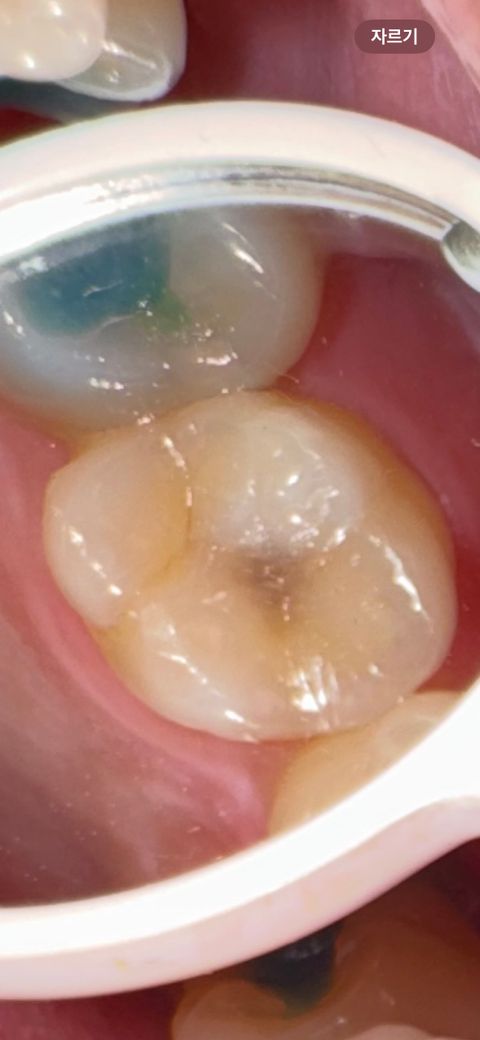

윗 어금니이구요 충치랑 크랙이 보이는데

레진으로 충치만 얘기하셔서요

크랙은 상관없을까요?

그리고 다른 의사선생님들이 볼 때에도 신경치료까지는 안해도 될까요 새벽에 불안한 마음에 올립니다

일단 충치범위가 커 보이지 않아 충치치료만 해도 될 것으로 보입니다. 신경치료 여부는 x-ray 보아야 진단할 수 있습니다.

충치는 잇어 보이는 크랙은 괜찮은거 같습니다 .충치가 깊을꺼 같으니 일단 엑스레이 촬영도 해보셔야될것같습니다 .

충치와 금이 같이 있는 치아라면 충치와 금을 제거하고 난 다음에 신경이 노출되지 않는지를 확인하는 것이 좋습니다. 신경이 노출이 된다면 신경치료가 필요하며 신경이 노출되지 않는다면 신경 치료를 하지 않고 보철 치료를 할 수도 있습니다.

자세한 확인을 위해서 치과에서 진료를 받아보는 것을 권유드립니다.

크랙이 깊지 않고 표면에만 있는 경우 크랙라인까지 확대하여 레진치료를 하는 경우도 있습니다